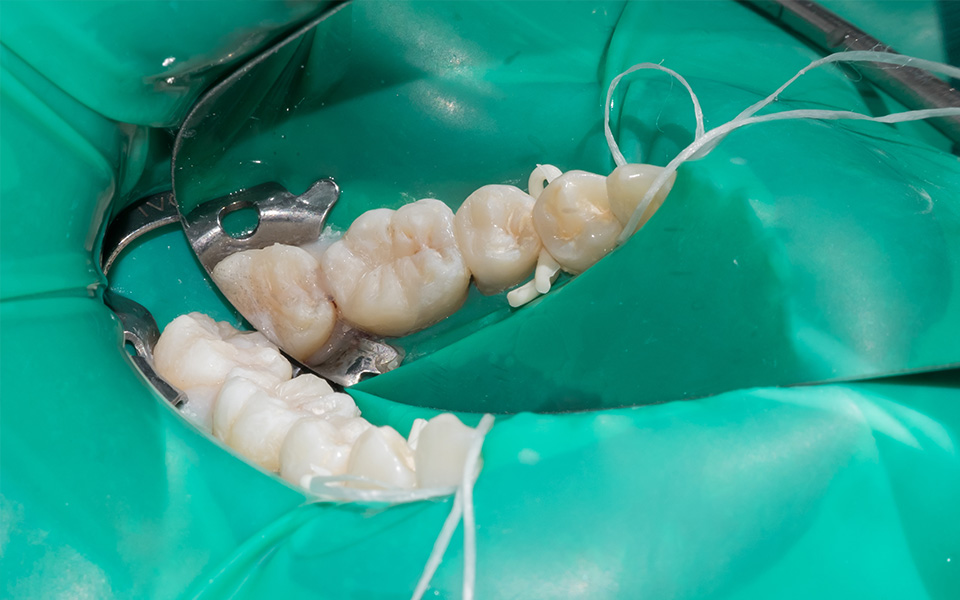

口腔内にはさまざまな細菌が存在し、根管治療中に唾液を介して内部に入ってしまうと、再発のリスクは50%まで高まると言われています。このリスクを回避するために、当院では、根管治療など神経の治療時には「ラバーダム」というゴムシートを使用しております。ラバーダムを装着すれば、再発のリスクは10%以下まで下げることができます。また、治療中(特に奥歯の治療)は舌や頬が邪魔になり、治療がしにくい場合がありますが、ラバーダムを装着することで歯だけを露出させることができ、根管治療の精度を高めることから、ラバーダムは根管治療では必須器具となります。

治療前

治療後

| 主訴 | 虫歯を治したい |

|---|---|

| 治療期間 | 1回 |

| 費用 | 再根管治療132,000円(税込)+ ファイバーコア44,000円(税込)= 176,000円(税込) |

| 治療内容 |

ラバーダムを用いて無菌的な環境下で再治療(過去に根管治療をしている歯の治療)を行いました。 過去に詰めた修復物の周りが虫歯になってしまっていたため、マイクロスコープ下で虫歯を完全に取り切り、 NiTiファイルを用いた根管形成、薬液や超音波器具による洗浄、体に馴染みの良い材質による充填、被せ物を支え、再感染しないように土台を立てました。 |